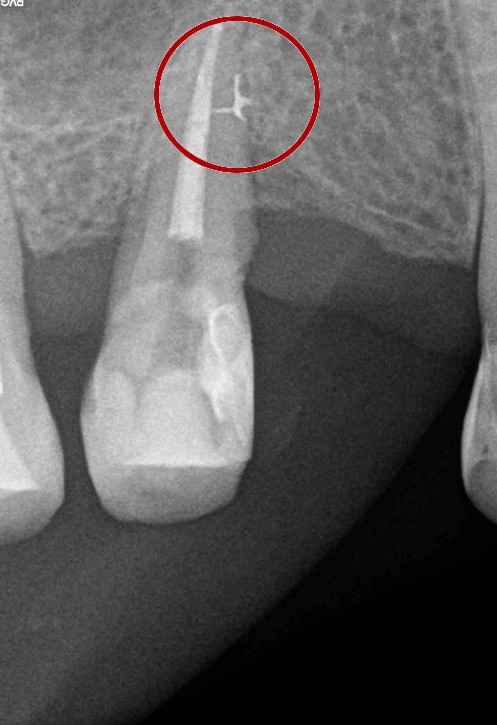

W przypadku zaawansowanych postaci zapaleń miazgi oraz zapalenia tkanek okołowierzchołkowych obraz radiologiczny jest warunkiem rozpoznania. W takiej sytuacji standardem diagnostycznym są zdjęcia przylegające zęba, często wykonywane przy użyciu radiowizjografii na fotelu stomatologicznym w trakcie leczenia zęba. Przydatne jest również badanie RTG OPG pantomograficzne, które pokazuje w dwuwymiarowym obrazie zarówno uzębienie, jak i cały układ kostny szczęki oraz żuchwy.

By uniknąć niedokładności leczenia, oprócz sumiennego wykonania procedur należy diagnostycznie kontrolować każdy etap leczniczy przy użyciu rtg. Szansą dla niedokładnie wypełnionego kanałowo zęba jest jego powtórne leczenie endodontyczne, zwane REENDO.

Konieczność powtórnego leczenia endodontycznego może zaistnieć w sytuacji, gdy kanały zęba nie zostały wypełnione do ich anatomicznego wierzchołka lub w trakcie leczenia doszło do złamania i pozostawienia ułamanego narzędzia w świetle kanału korzeniowego. O konieczności powtórnego leczenia endodontycznego może również zadecydować zmiana zapalna przy wierzchołku korzenia, która jest widoczna jedynie na obrazie kontrolnego zdjęcia rtg.